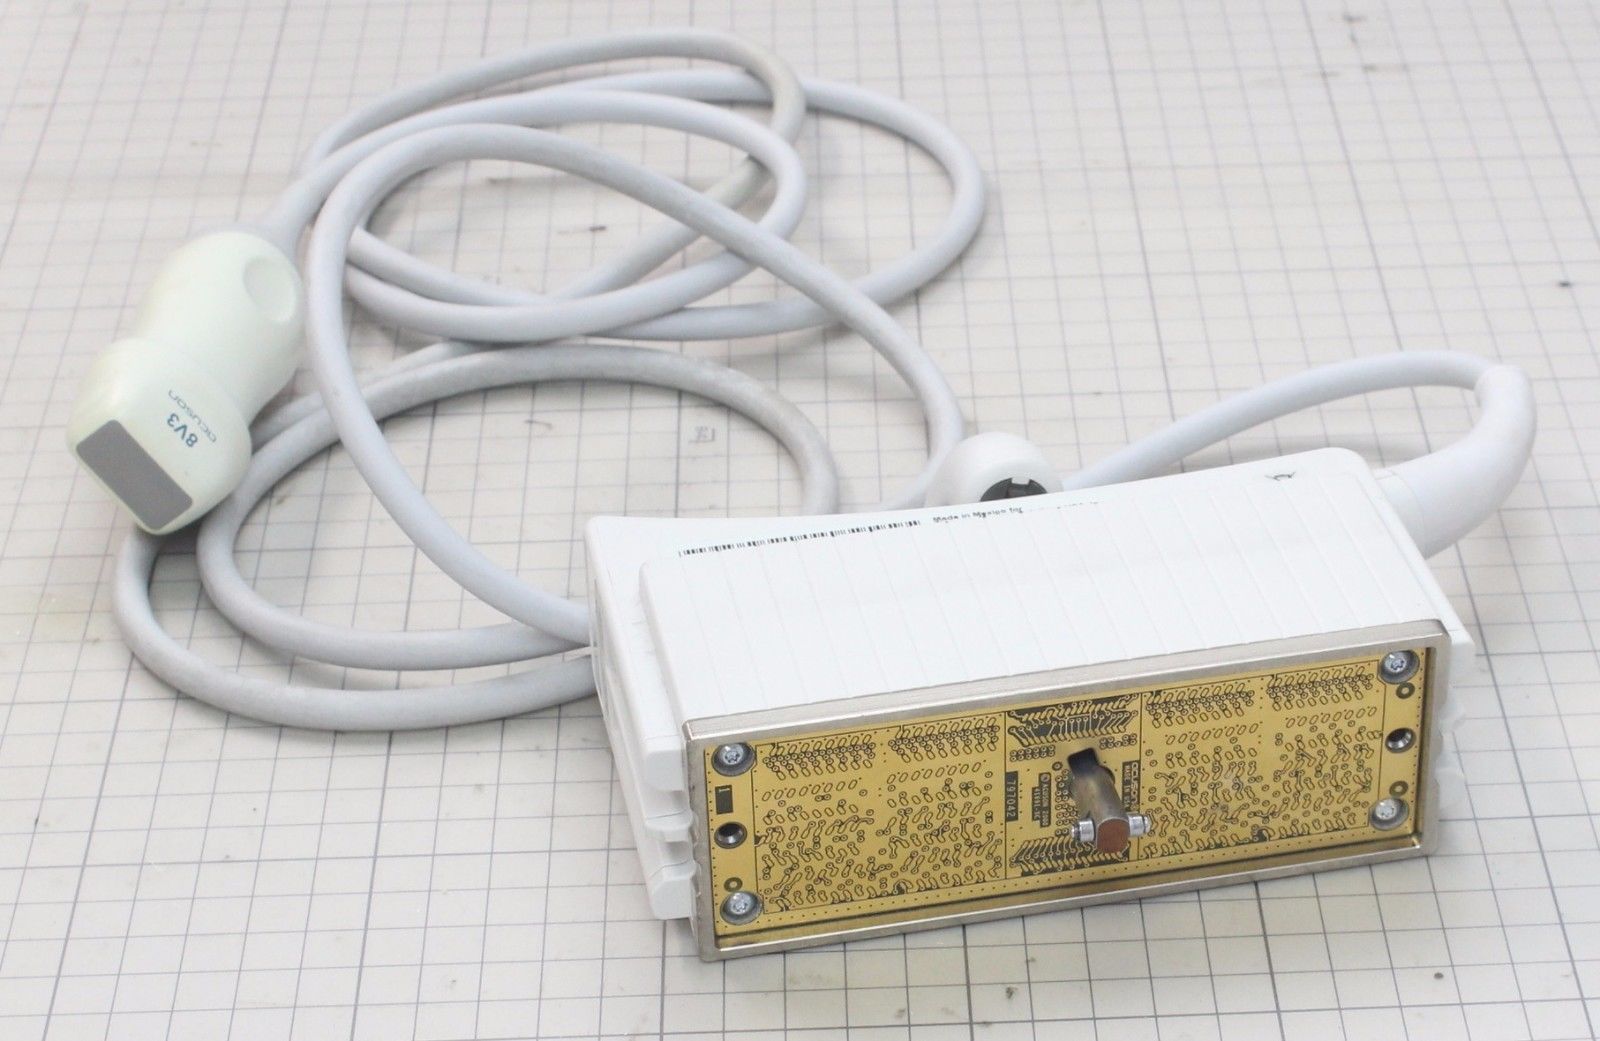

Acuson Probes

DIAGNOSTIC ULTRASOUND MACHINES FOR SALE

Acuson Linear Ultrasound Probe 7L3 08267217